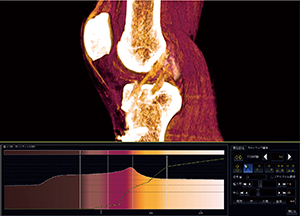

前十字靭帯不全断裂─術前および術後のCT

左膝前十字靭帯不全断裂の再建術を行った症例を紹介する。術前のCT検査はMPR画像と骨の3D画像が主な目的となり,術後のCT検査は骨孔の位置評価が主な目的となるが,本症例ではVR画像を用いて術前後の前十字靭帯の評価も行った(図4,5)。

術前のVR画像では,前十字靭帯の大腿骨付着側が菲薄し明瞭に描出されておらず,不全断裂の所見を示している。また,前十字靭帯断裂の間接所見として,脛骨の前方偏位や後十字靭帯のたわみも観察された。

術後では再建靭帯のCT値が周囲の軟部組織よりやや高く,靭帯自体が太いためVR画像で明瞭に描出できた。このようなVR画像が得られれば患者説明にも有用である。

術前のVR画像で断裂部が菲薄であったが,これに関してはWS上で表示ができていないのか,断裂を示す所見として表示されないのかを見極められるような画像を作成しなければならない。そのためには,靭帯の走行に対して最適な角度でカットし前後の情報も漏らさないことと,やはり画像ノイズの少ないデータを基にVR画像を作成し,オパシティカーブの調整で靭帯を明瞭に表現することが重要になる。

図4 左前十字靭帯再建術術前のVR画像と |

図5 左前十字靭帯再建術術後のVR画像と |